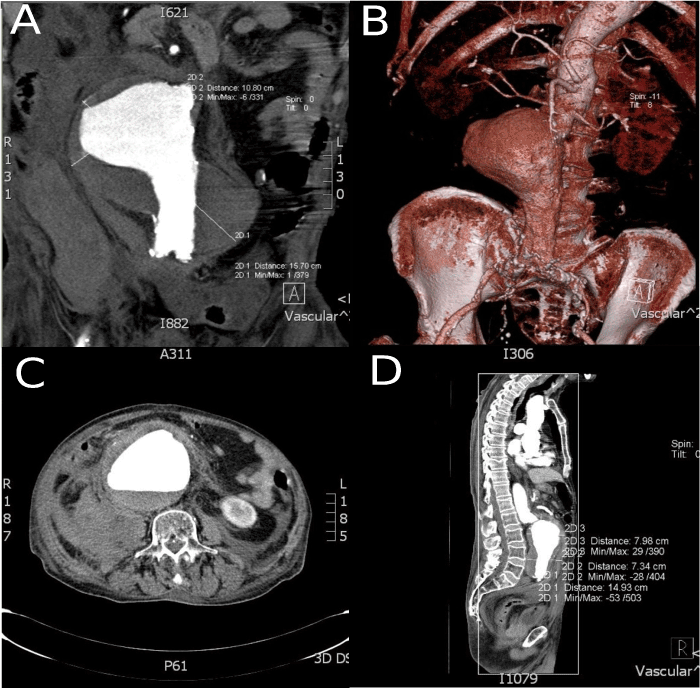

A 78-year old man with a medical history of smoking, hyperlipidemia and hypertension was admitted to our department with ruptured abdominal aortic anerysm (AAA) dignosed by ultrasonography of  the abdomen. The blood pressure was 60/20 mm Hg. An emergent computed tomography scan of the abdomen revealed a rupture of a giant infrarenal AAA of 16 cm in diameter with extensive intraluminal thrombus, evidence of rupture and large intraabdominal hematoma (Figure 1). Abdominal computed tomography angiography (CTA) with contrast showed a ruptured giant infrarenal AAA measuring 16x11 cm with a large mural thrombus and intra-abdominal hematoma compressing intra-abdominal organs (Figure 1)

Figure 1. Rupture and large intraabdominal hematoma

The patient underwent a succeful open surgical repair with placement of a Dacron tube graft 18 mm (Figure 2). Postoperative CTA with contrast showed complete sealing of the aneurysm with no endoleak detected (Figure 2). The patient was transfered to the intensive care unit following successful surgical repair. Patient was transfered to the department of cardiovascular surgery on postoperative day 2. Postoperative recovery resulted in hospital discharge at postoperative day 12.

Figure 2. Dacron tube graft